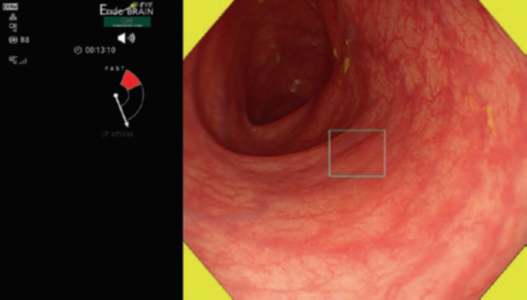

By using the diagnostic flowchart of the JES-BE classification (. Fig. 1), first, the mucosal pattern was classified as “visible” or “invisible” and rated as “regular” or “irregular” based on the diagnostic criteria for irregularity, as reported previously. The “invisible” mucosal pattern cannot be rated. Second, the vascular pattern was classified as “visible” or “invisible.” The “visible” vascular pattern included normal- appearing, long branching vessels and GTV previously reported and after- mentioned. General diagnosis was rated as “regular” or “irregular” based on mucosal plus vascular patterns. Finally, histology (“non-dysplastic” vs. “dysplastic”) was predicted according to the general diagnosis. “Dysplastic” corresponds to SBERN, including low-grade dysplasia (LGD), high-grade dysplasia (HGD), and superficial adenocarcinoma. Representative NBI-M images are shown in Fig. 4.